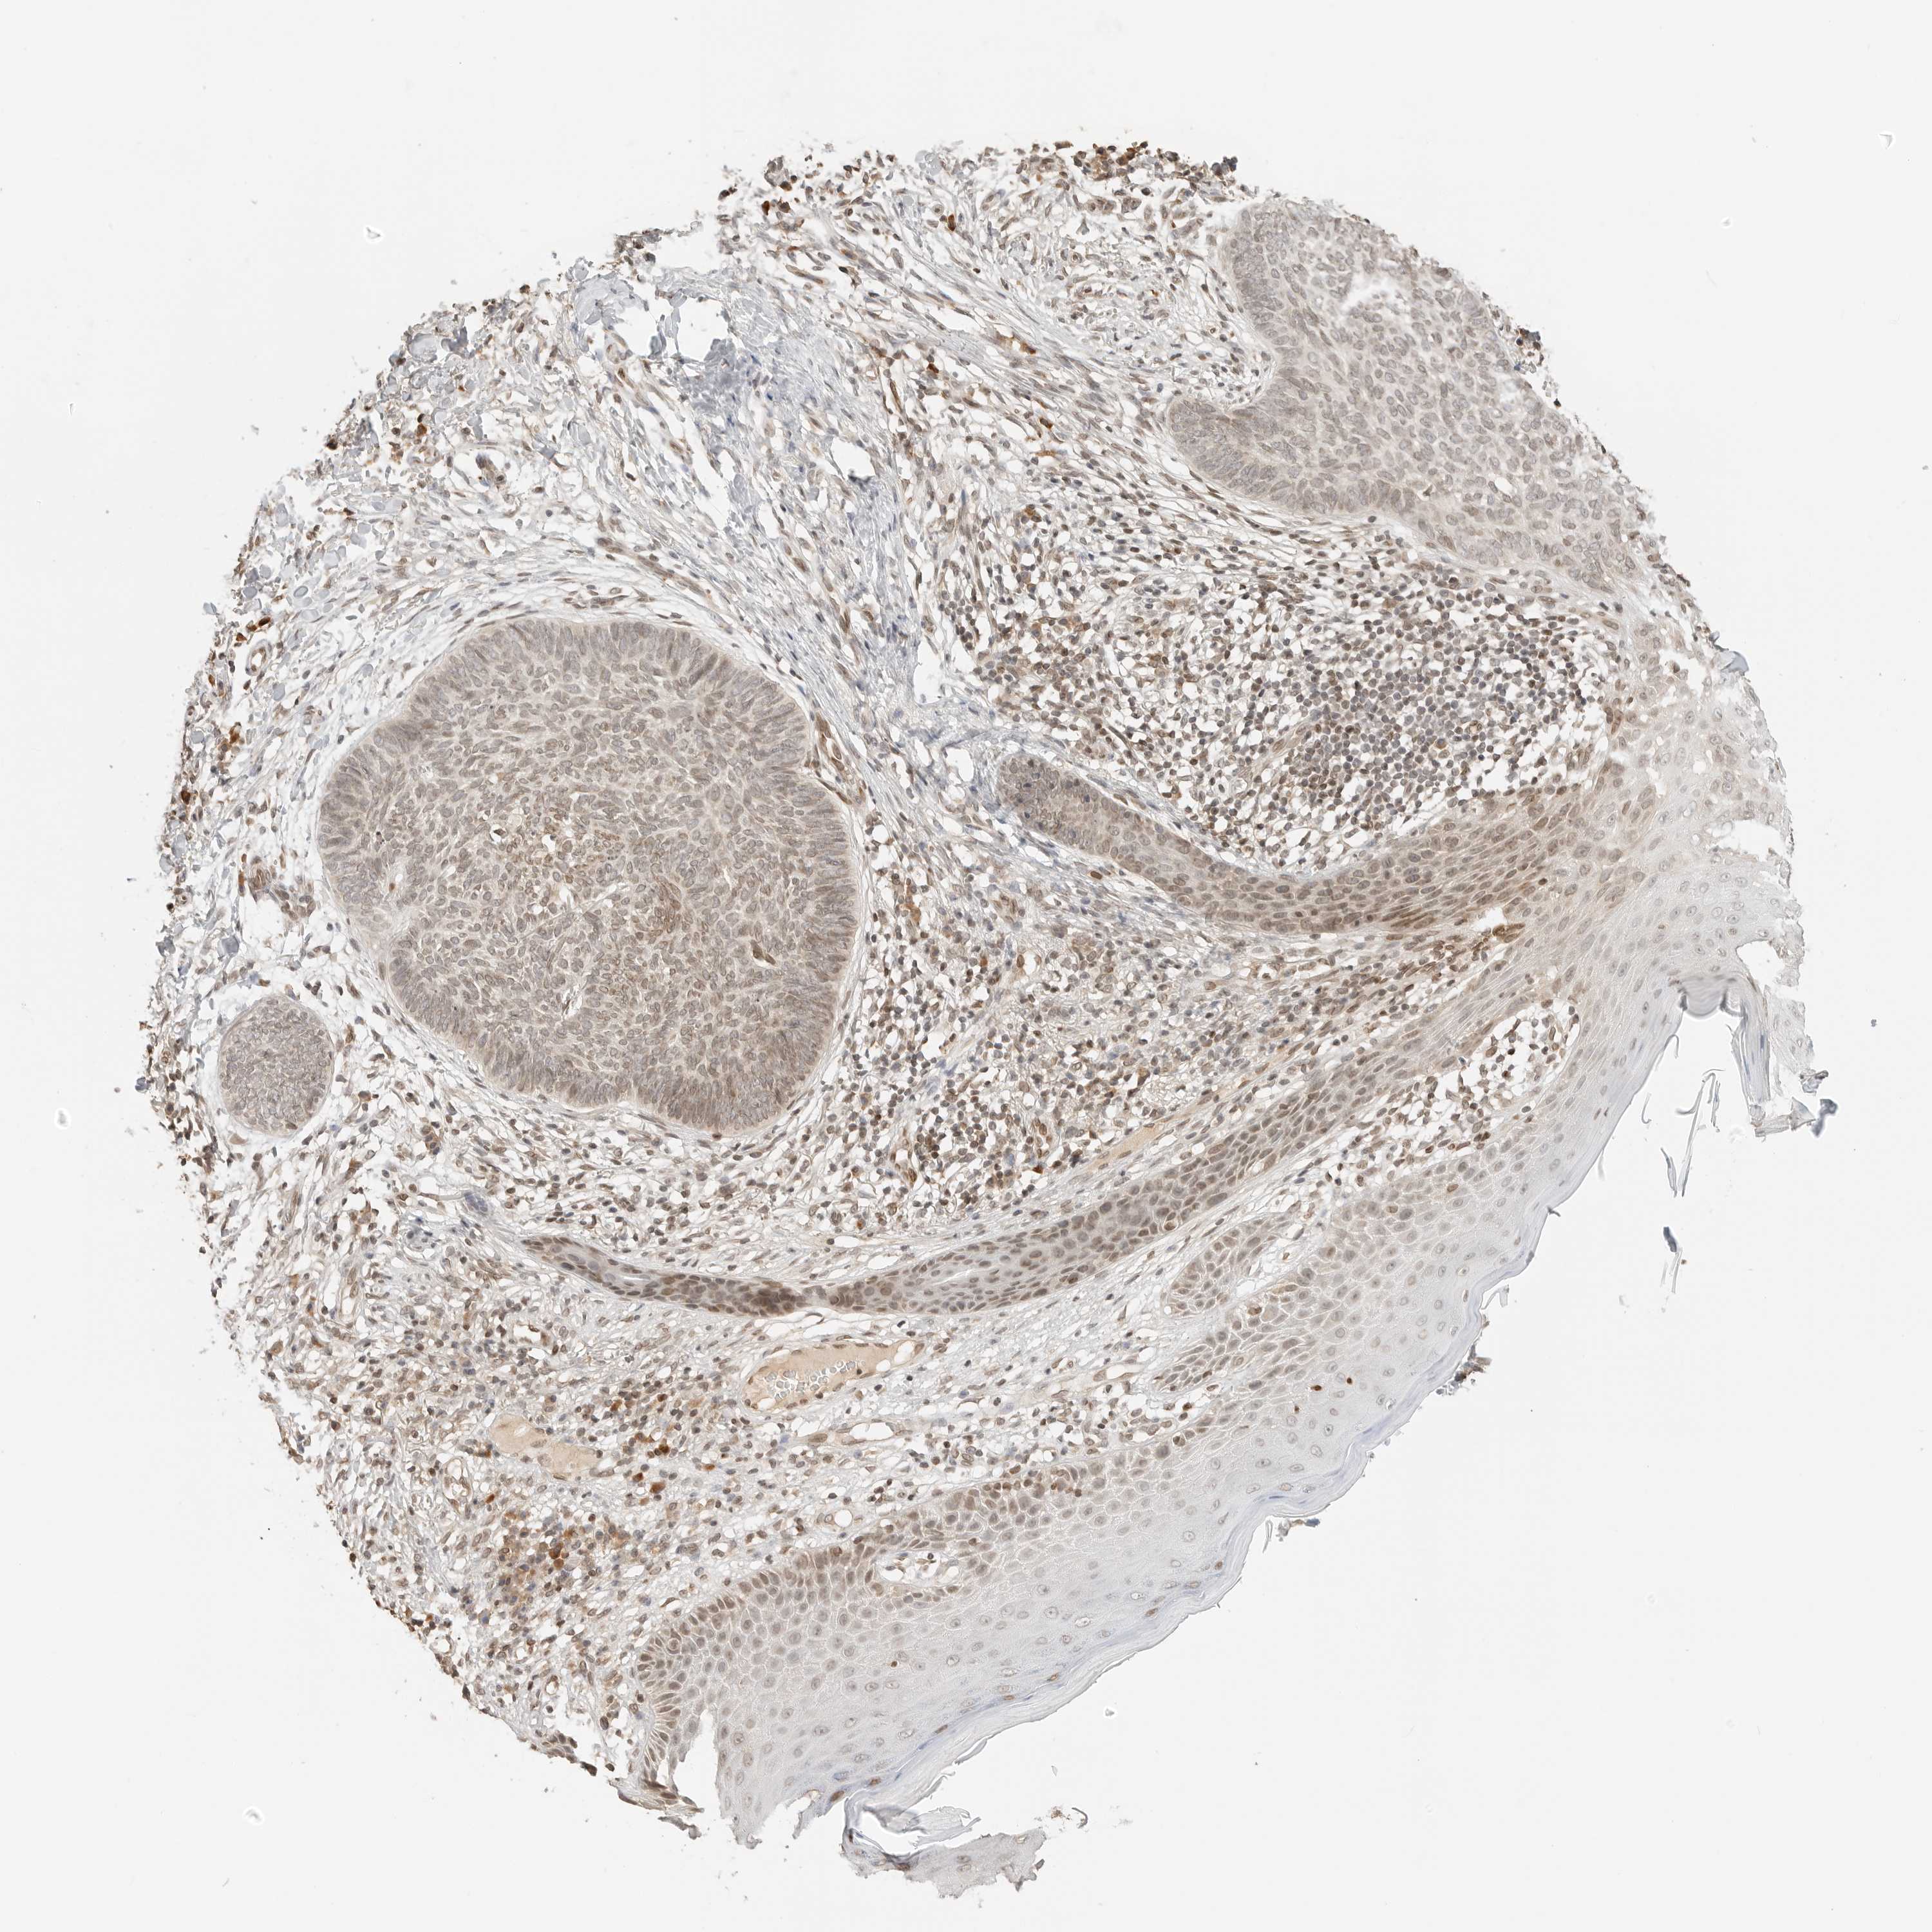

SKIN CANCER - Protein expressioni

A mouse-over function shows sample information and annotation data. Click on an image to view it in a full screen mode. Samples can be filtered based on level of antibody staining by selecting one or several of the following categories: high, medium, low and not detected. The assay and annotation is described here.

Antibody stainingi

Antibody staining in the annotated cell types in the current human tissue is reported as not detected, low, medium, or high, based on conventional immunohistochemistry profiling in selected tissues. This score is based on the combination of the staining intensity and fraction of stained cells.

Each image is clickable and will lead to virtual microscopy that enables deeper exploration of all samples and also displays staining intensity scores, fraction scores and subcellular localization as well as patient and tissue information for each sample.

Antibody HPA006721

Staining

High

Intensity

Quantity

Location

Squamous cell carcinoma, NOS